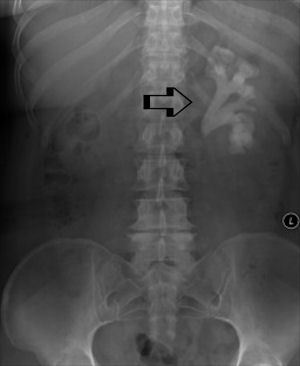

Imagem: calcificação sacro-iliaca, coluna em bambu, osteofitos calcâneo

Homem, idoso, negro, com queixa de dor lombar crônica, sem irradiação, que piora aos esforços, associado a cansaço e dispneia aos esforços, perda de peso, urina espumosa, anemia. Rx com lesões líticas arredondadas em coluna lombar…